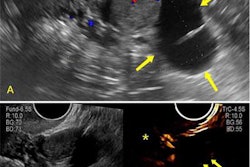

Researchers led by Eva María Soto-Sánchez, PhD, from Hospital Universitario Infanta Leonor in Madrid found significantly higher placental thickness, placental venous lake frequency, and umbilical vein flow values in pregnant women with the coronavirus.

The researchers found higher placental thickness and a higher frequency of placental lakes in the SARS-CoV-2. Additionally, they found higher mean velocity umbilical vein and umbilical vein blood flow in this group than in the control group.

| Placental findings among pregnant women with SARS-CoV-2, healthy control | |||

| Measure | Healthy controls | Pregnant women with SARS-CoV-2 | p-value |

| Mean placental thickness | 33.82 | 53.82 mm | < 0.001 |

| Frequency of more than four placental lakes | 6.36% | 50.91% | < 0.001 |

| Mean velocity umbilical vein | 10.81 cm/s | 12.45 cm/s | 0.001 |

| Mean umbilical vein blood flow | 305.5 ml/min | 389.9 ml/min | 0.05 |